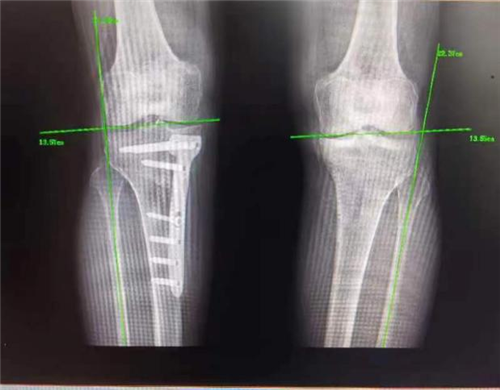

而近期患者感觉其左膝关节疼痛逐渐加重,伴随肿胀,甚至需要扶拐前行。因为患者对第一次手术效果非常满意,所以再次来到我院骨一科就诊。李强主任团队针对患者具体病情进行评估,发现患者负重位X线片显示左膝关节内侧间隙变窄,胫骨内翻,胫骨近端后倾角 76°,胫骨近端内侧角小于82°,左膝关节退行性改变。外侧间室及外侧关节间隙相对完好,测量后发现其畸形主要为关节内翻畸形。

(术前)

手术如期进行,在骨科手术机器人“透视眼”和“稳定手”的精准操作下,患者术中测量内翻畸形纠正,胫骨近端后倾角92°。术后,患者左膝疼痛明显缓解,关节活动度较术前明显改善,术后3天即扶拐下地行走,4周后即可完全负重。

(术后)